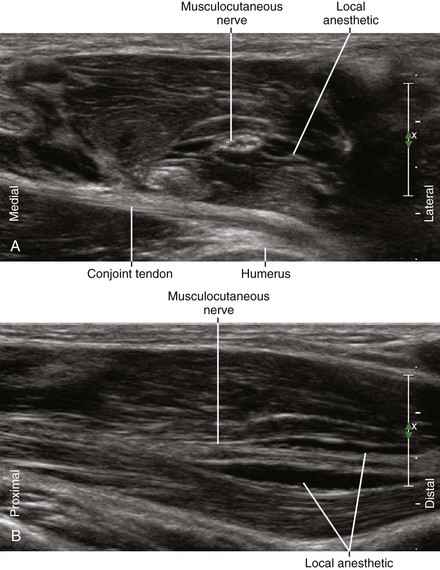

Ultrasound imaging of the musculocutaneous nerve in the axilla can be used to facilitate regional block.2 This directly addresses one of the primary weaknesses of traditional axillary block.

The lateral course of the nerve and its changes in shape as it passes through the coracobrachialis muscle are characteristic features that allow ultrasound identification of the nerve.3 The nerve typically has a flat shape within the coracobrachialis muscle; therefore, this is a desirable location for regional block. The relatively high surface area–to–volume ratio may improve onset kinetics of the block.

| Approach | SAX view of MCN, in-plane from lateral to medial |

| Place the needle tip at lateral corner of MCN within CBr. | |

| Sonographic assessment | The injection should track along the MCN within CBr. |